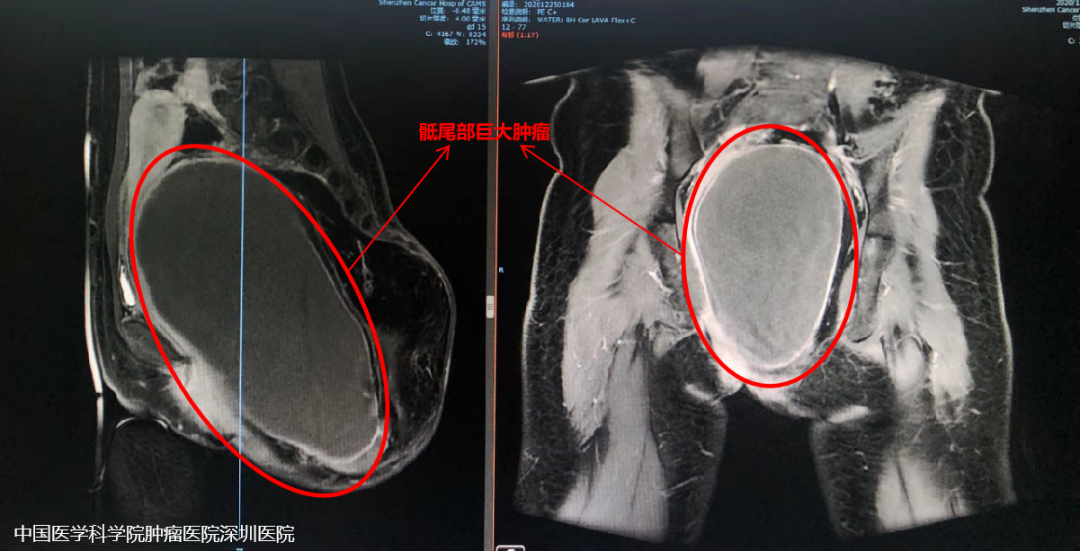

巧巧就诊时,肿瘤的压迫已经让她跛行、行动不便,排尿、排便困难,这个肿瘤已经到了必须治疗的地步。这种最大径接近30cm的巨大畸胎瘤可以说是很罕见的,手术风险极高,可能会出现肠道损伤、膀胱尿道损伤、生殖系统损伤、血管神经损伤、大出血、甚至失血性休克等。 骶尾部巨大肿瘤切除对外科医生来说一直是个极大的挑战。经科室讨论后向医务部报备重大手术申请,在王绿化院长、王东文副院长的主持下,总院骨科许宋锋教授立即会同泌尿外科王东文副院长及姜焕荣教授、妇科孙力教授、麻醉科李泉教授、介入治疗科宋鹏教授、胃肠外科李景文教授、骨科付来华教授等进行多学科讨论。 术前影像资料 制定了严密的手术计划——术前介入科行供瘤血管栓塞及腹主动脉球囊植入(以备术中临时阻断血供),麻醉选择控制性降血压以减少出血,妇科、泌尿外科及胃肠外科护航,在腹主动脉球囊阻断下行单纯后路骶尾部巨大肿瘤切除术。 本手术主要难点: 1.预防大出血——术前肿瘤血管栓塞、术中球囊阻断及控制性降血压。 2.术中注意保护结直肠、子宫、卵巢、输尿管、腰骶部神经和髂血管等。 3.肿瘤切除后盆底肌肉的修复和重建等。 术前栓塞 制定计划后,由骨科付来华教授主刀,许宋锋教授、介入治疗科宋鹏教授联合,2021年1月在全麻下进行了“骶尾部巨大软组织肿瘤切除 + 盆底软组织修复 + 血管神经探查松解”手术,手术时长近6小时,出血不足400ml。手术完美保护了盆腔重要脏器(直肠、子宫、尿道等),避免了术中大出血及骶尾部神经损伤。 “定时炸弹”顺利切除 肿瘤多学科诊疗很关键 巧巧的手术很成功,术后恢复也很好。现在巧巧终于摆脱了这个困扰了她25年的阴影,开开心心迎接她的新生活。第一次复查的她,已经穿上了漂亮的衣服,重拾自信。 主管医生介绍,畸胎瘤可能与胚胎期生殖细胞异常分化等因素有关,发病率为1/40000至1/20000,女性多发,发病率是男性的3-4倍。 畸胎瘤是先天性疾病,最常见的部位是卵巢,但发生于骶尾部是非常罕见的。此次手术难度巨大,最终通过多学科的努力,不仅完整的切除肿瘤,而且很好的保护了盆腔内的脏器。对于年轻的巧巧来说,本次手术也不会影响她的生育功能。 专家建议,在发现异常肿物或肿瘤时,避免盲目就医,有针对性的找到肿瘤专科医院就诊,避免延误就医导致病情恶化。 777全讯白菜网的多学科诊疗模式对于肿瘤的“精准治疗”和“个体化治疗”具有重大意义。